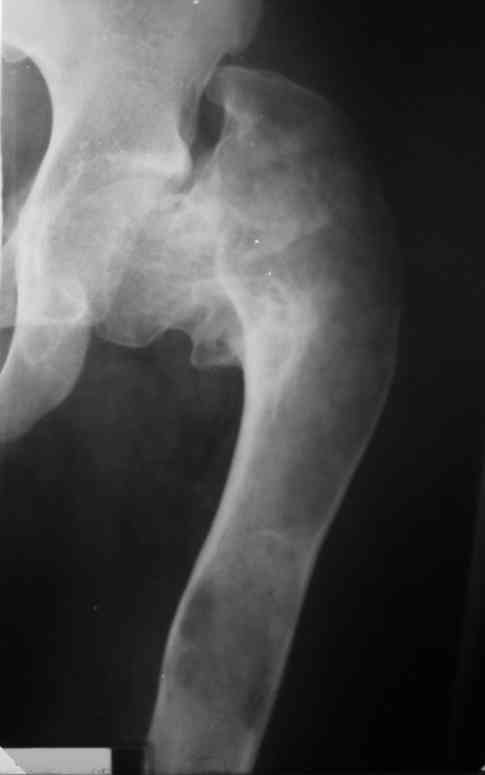

Интересует возможность одномоментного устранения очага ФД и корригирующей остеотомии, хотя я склоняюсь к двухэтапной тактике.Когда я впервые увидел этого подростка, сразу после снятия гипсовой повязки, консолидации не было и в планах была экскохлеация с медиализирующей вальгирующей остеотомией. Сейчас, когда консолидация отчетливая, возможно ограничимся только вальгизацией.На мой взляд надо оствить приемлемые условия для последующего ТЭП. Удивляет столь закрепившееся в практике мнение о возможности спонтанного восстановления костной после патологических переломов при кистах и ФД.

Около 16 лет наблюдаю пациента с ФИБРОЗНОЙ ДИСПЛАЗИЕЙ левой нижней конечности, полиосальная форма. Прилагаю рентгенснимки.